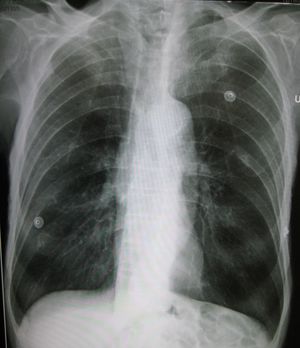

| A lateral chest x-ray of a person with emphysema. Note the barrel chest and flat diaphragm. | |

شعر المريض بصعوبة في التنفس وخصوصًا في أثناء الزفير (التنفس السطحي) وتوسّع في الصدر وزرقة الجلد بسبب نقص الأكسجين. يشكو المصابون بهذا المرض من نزلات البرد المتتابعة ومن التهاب الرئة. كما يتسبب في نشوء أمراض القلب عند بعضهم.